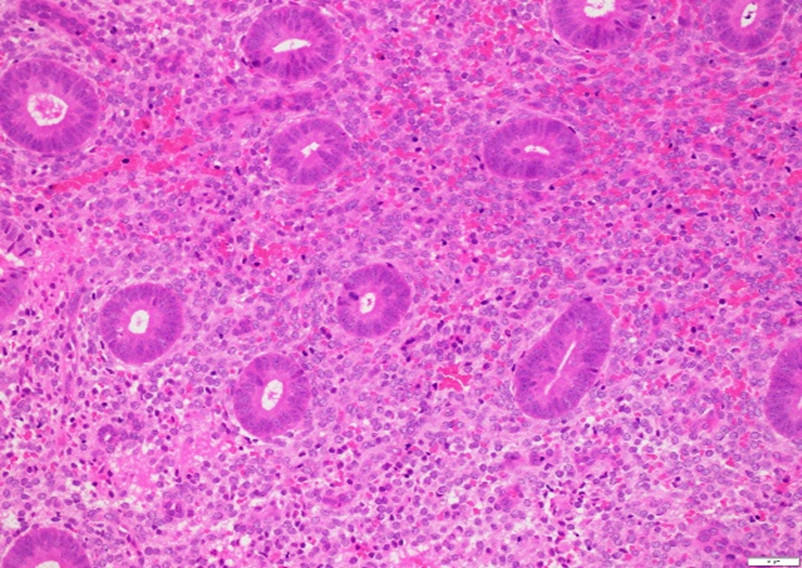

The gold standard for diagnosing endometriosis is to use histochemistry to detect plasma cells on the endometrial staining smear. Methods such as HE histochemistry are often difficult for even specialists because the endometrium contains many cells with different morphology that can make reading difficult. Therefore, an immunohistochemistry method based on the appearance of the cytoplasmic marker CD138 (also known as syndecan-1) has been developed to diagnose endometritis.

Currently, the diagnosis of CE is usually using immunohistochemistry with the CD138 marker. The use of this method has many advantages over the HE method. In the HE method, monocytes and plasmacytic stromal cells can be mistaken for plasma cells, resulting in an increased false-positive rate. Furthermore, the use of CD138 also makes it easier to count plasma cells (since plasma cells are very visible in the field), reducing the time required to do the test. Therefore, compared with HE staining, the use of CD138 is a more reliable method.

(Figure 1 - right) Immunohistochemistry detected plasma cells by the CD138 marker compared with HE staining (Figure 2 right)

Bayer-Garner et al. studied on 47 patients using HE and CD138 staining. While HE staining detected 7 cases of HFMD, using CD138 detected 13 more cases [3]. Another study showed that CD138 immunohistochemistry was more detectable than HE staining and morphological methods (56% vs 13%, P < 0.01) [4 ].

To be able to conclude the status of CE in fact needs evidence related to the morphology of endometrial cells, so the test at Gentis performed in combination with the determination of plasma cells by immunohistochemistry staining. CD138 and HE staining to determine cell morphology.